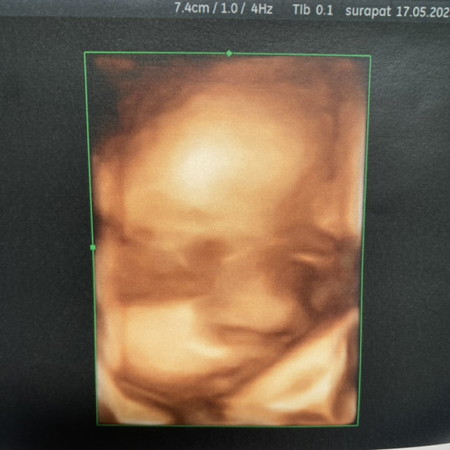

34+3 ยังซาวด์เห็นหน้าอยู่ครับ🥰

แม่ ๆ ซาวด์ 4D ถึงกี่วีคกันคะ